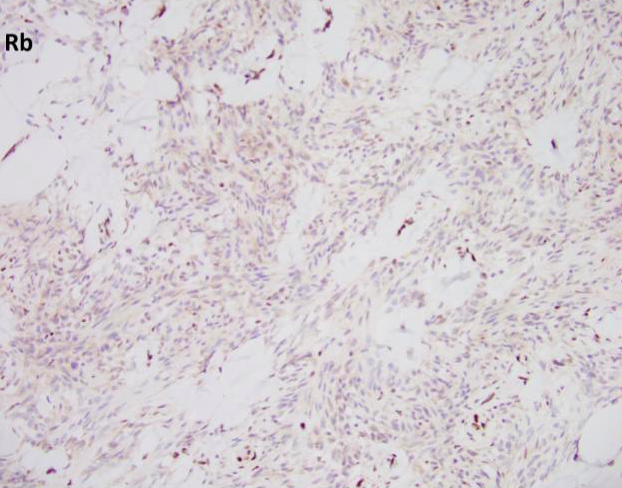

Myofibroblastoma (MFB) is an uncommon myofibroblastic lesion, typically seen in older patients. It occurs in both males and females and usually presents as a slow growing, palpable, painless breast mass. Most lesions are small, 1-4 cm; however, cases of giant myofibroblastomas have been reported. Histologically, the lesion is characterized by a well-circumscribed mass composed of spindle cells intermixed between bundles of hyalanized collagen. Because the neoplasm is myofibroblastic in origin, immunohistochemical markers such as Smooth Muscle Actin (SMA), Muscle Specific Actin (MSA), and Desmin are characteristically positive. Myofibroblastomas are also typically positive for CD34, estrogen receptor (ER), progesterone receptor (PR), and androgen receptor (AR). The cells of interest are negative for cytokeratins. Genetically, the entity is characterized by loss of 13q14 and 16q. As a result, there is inactivation of genes RB1 and FOXO1, and as such, loss of Rb expression via immunohistochemistry. Treatment typically consists of surgical excision with no additional therapy required.

All of the other answer choices may be considered in the differential diagnosis, especially on biopsy. Metaplastic carcinomas can be comprised of spindle cells with or without an epithelioid component. However, the stromal collagen is typically not present and the cytology is much more pleomorphic with frequent mitosis and an infiltrative growth pattern. Additionally, metaplastic carcinomas will be positive for cytokeratin immunohistochemistry and negative for hormone receptors ER/PR/AR, CD34, and desmin/myofibroblastic markers. Phyllodes tumors are also neoplasms of stromal differentiation. Phyllodes tumors, however, show both the presence of spindle cells and benign epithelium, typically creating a “leaf-like” architecture. IHC is positive for CD34 but Rb staining is retained. Pseudoangiomatous stromal hyperplasia (PASH) usually doesn’t form a mass; however, it is a myofibroblastic lesion with a similar staining pattern, SMA, desmin, ER, and PR positive. Histologically PASH has a dense collagenous stroma with prominent slit-like spaces. Additionally, the characteristic genetic alterations found in MFB are not present.